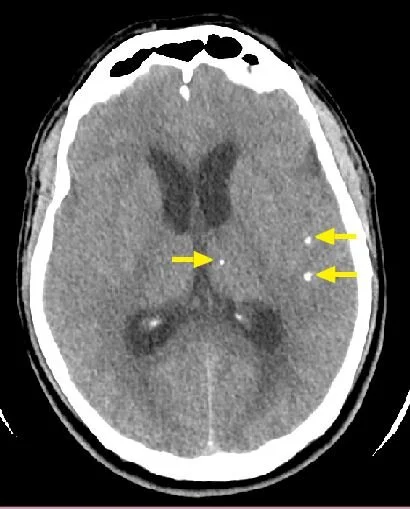

neurocysticercosis

hyperdense/calcified on CTH

hypointense core on MRI with edema, can rim-enhance